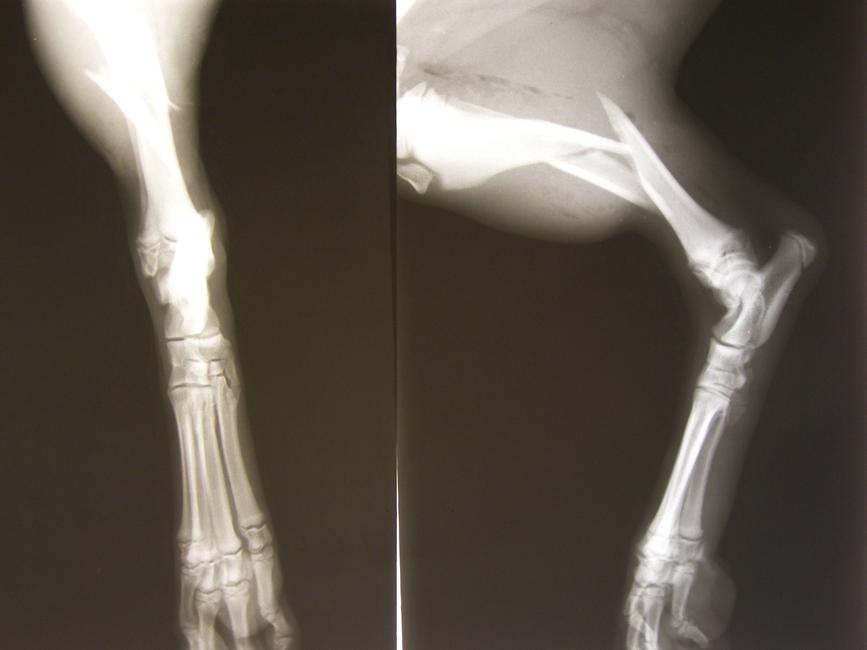

Cette technique permettrait de soigner les fractures sans tous les désagréments liés à la greffe osseuse habituelle

Et si les cellules souches permettaient de soigner les fractures ?

Cette technique innovante, qui pourrait remplacer la greffe de moelle osseuse, va être testée à l'échelon européen.